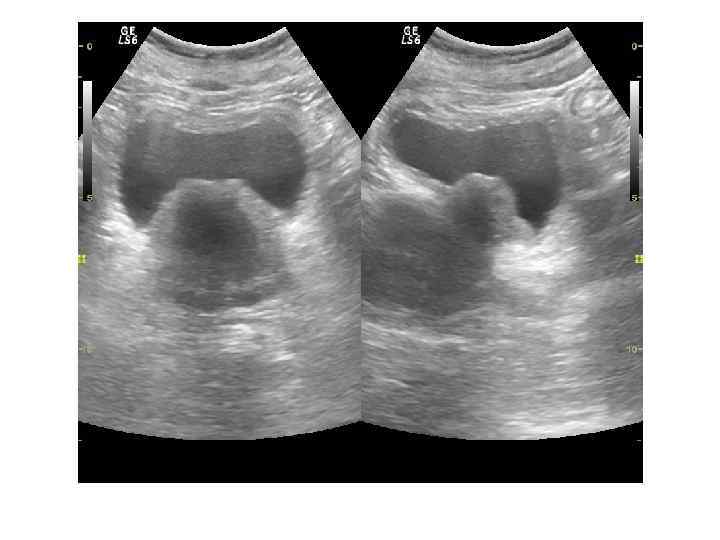

Доступы: трансабдоминальный, трансперинеальный, трансректальный, трансуретральный Трансабдоминальное исследование производится с помощью датчиков 3, 5— 5, 0 МГц и требует наполнения мочевого пузыря. При трансабдоминальном исследовании можно определить размеры и объем предстательной железы, выявить изменения, характерные для ДГПЖ, и определить особенности роста аденоматозных узлов. Не используется для выявления рака простаты. Трансперинеальное (чреспромежностное) исследование простаты: датчик 3, 5— 5, 0 МГц устанавливается на промежность. Исследование проводится при невозможности выполнения трансабдоминального или трансректального исследований. Качество визуализации не лучше чем при трансабдоминальном

При ТРУЗИ объем простаты может быть определен с помощью нескольких методов: 1. Объем =А х В х С х 0, 52 (рис. 6. 5 А), где А — продольный размер, В — переднезадний размер, С — поперечный размер. Поперечный размер железы определяется при поперечном сканировании в ее средней части, переднезадний и продольный размеры — при сагиттальном сканировании 2. Объем = С 2 х В х 0, 52 где В — передне-задний размер, С — поперечный размер. 3. Объем = С 3 х 0, 52 где С — поперечный размер.

Нормальные размеры простаты